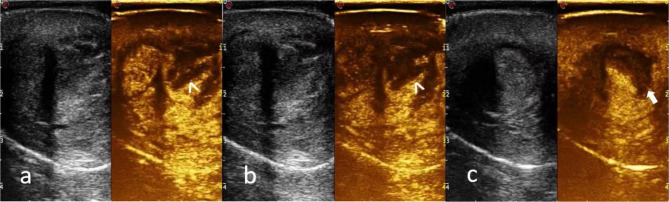

Fig. 4.

a, b CEUS shows a large abscess located in the ventral side of the middle and distal part of the cavernous body (arrowhead) and extended up to the distal dorsal side of the cavernous body (arrowhead) with the interruption of the albuginea tunic (arrow)